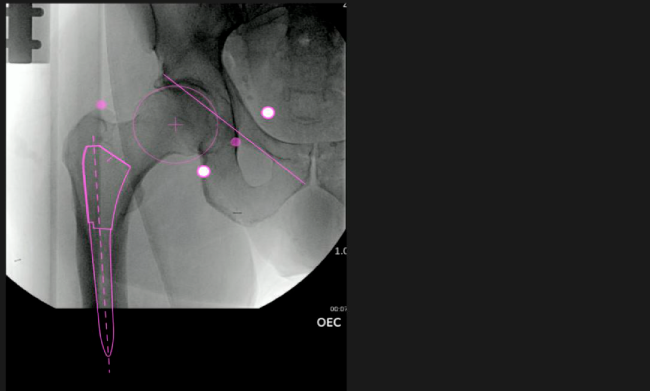

Mayor nivel de información intraoperatoria facilita la colocación correcta de los implantes:

Inclinación y anteversión de la copa acetabular para una correcta colocación del implante.

Verificación de la posición deseada del implante que potencialmente puede ayudar a reducir la probabilidad de dislocación protésica y aumentar la estabilidad de la articulación.

Anotaciones digitales y herramientas de análisis de longitud de pierna.